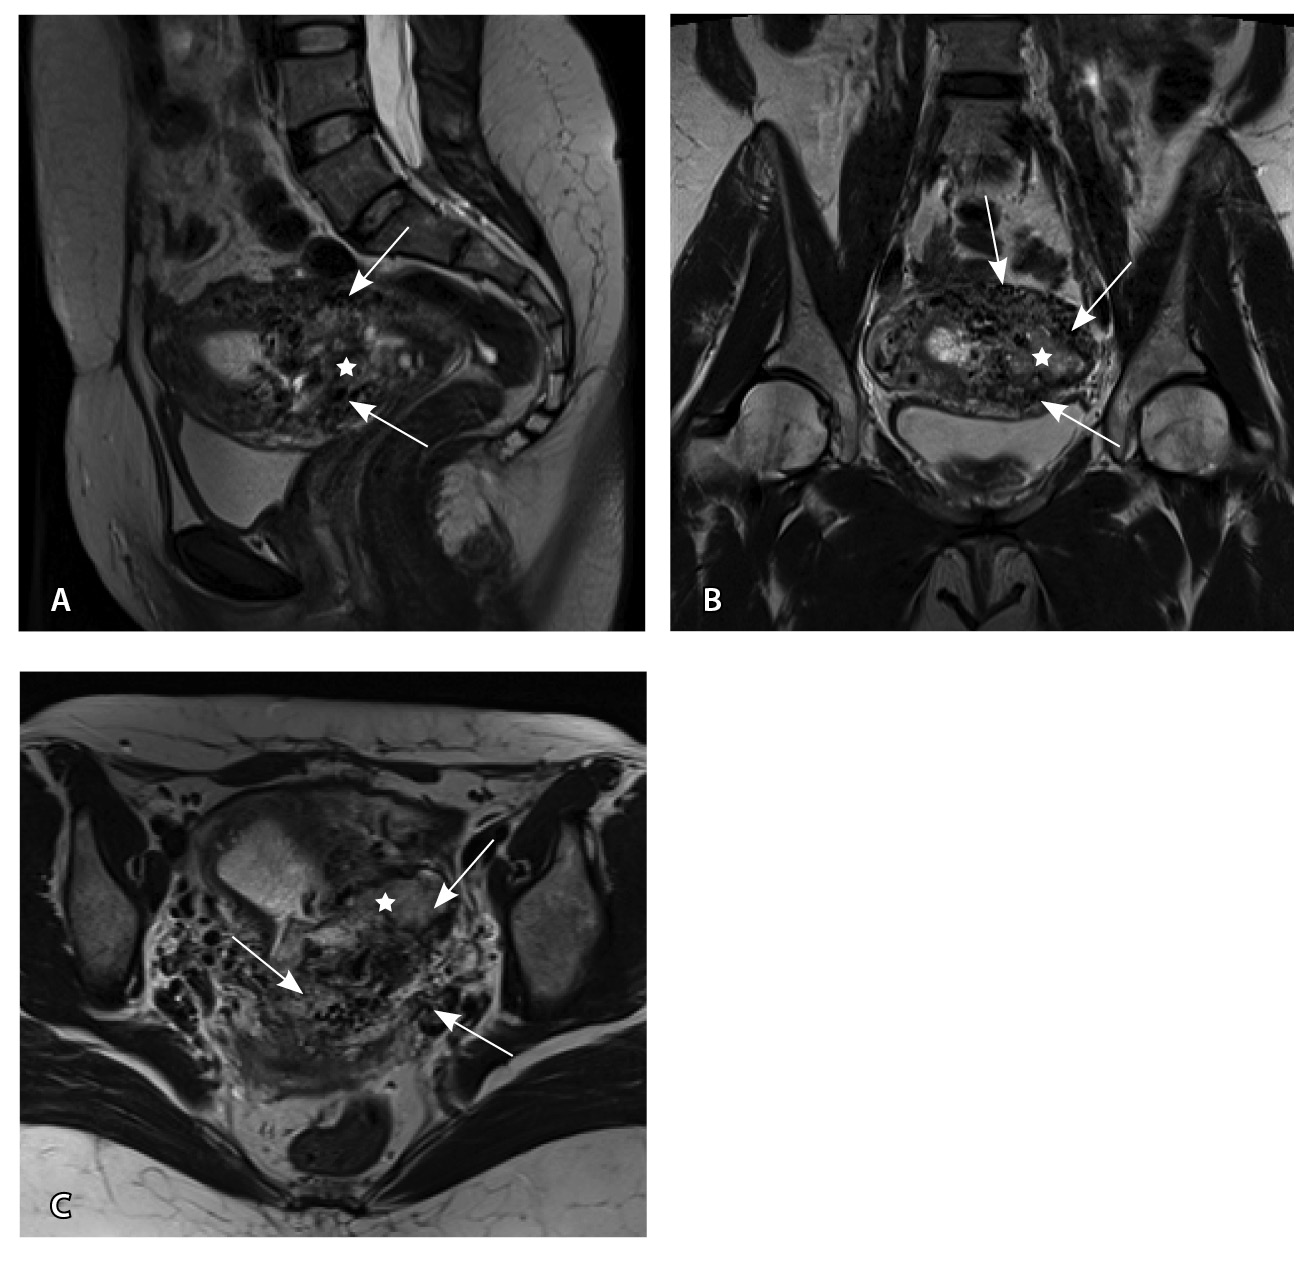

По наружной поверхности нижнего маточного сегмента и в параметрии определяется наличие полнокровной сосудистой сети с артериовенозными анастомозами. При контрастировании визуализируются фрагментарные участки гиперваскулярного накопления контраста вышеописанным образованием в рубцовой нише, а также определяется наличие артериовенозной сосудистой мальформации (рис. 2).

Рис. 2. Магнитно-резонансная томограмма, динамическое контрастное усиление в режиме Т1-взвешенного изображения FS. До контраста (А), в раннюю артериальную фазу (Б), паренхиматозную фазу (В), выделительную фазу (Г) определяются многочисленные патологические сосуды, зоны неоангиогенеза, сосудистые шунты как в стенке матки, так и в параметрии по типу артериовенозной мальформации

Для детализации сосудистого компонента артериовенозной мальформации, в том числе с целью планирования дальнейшей лечебной тактики, пациентке выполнено КТ-исследование (рис. 3). Обнаружено: тело матки увеличено, определяется образование в полости матки неясного генеза. В стенках матки сосудистая артериальная сеть с ранним сбросом контрастного вещества во внутреннюю подвздошную вену с двух сторон (диаметром 0,7 см справа, 0,8 см – слева), правую яичниковую вену (диаметром до 1,2 см), левую яичниковую вену (диаметром до 0,6 см).

Рис. 3. Компьютерная томограмма органов таза с контрастированием. Тело матки увеличено, в стенках матки сосудистая артериальная сеть (стрелки) с ранним сбросом контрастного вещества во внутреннюю подвздошную вену с двух сторон, правую и левую яичниковые вены (стрелка)